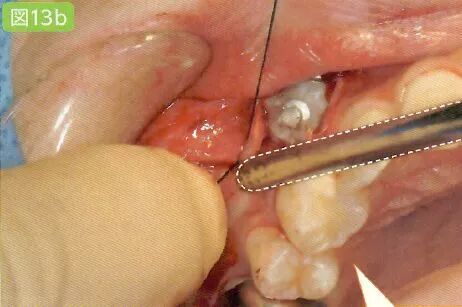

9缝合

切开的牙龈和牙槽粘膜用针缝合

有出血状况时保证缝合部位的术野

缝合时为了避免针尖刺伤粘膜,需要对舌头和颊粘膜进行排开

用针缝合前吸引牙龈

缝合前用吸唾器吸引切开线区域。缝合后,结扎并截断缝合线前,吸引从切口结扎处溢出的血液。

缝合舌侧牙龈时,为了避免患者的舌头触碰到针尖,根据主治医生的喜好可以使用简易的吸唾器,对舌头进行排开。

结扎之后用吸唾器吸引

特别注意,吸引过程可能会引起结扎松动。